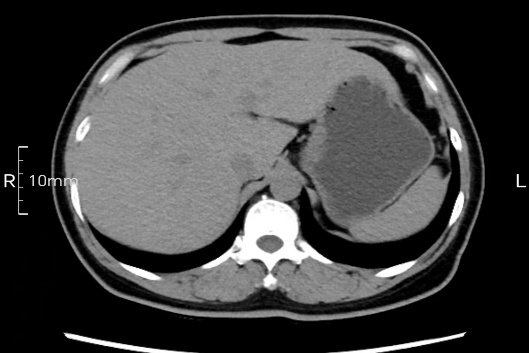

看看下面三幅便知遵醫(yī)囑的重要性。

禁食但檢查前沒(méi)有喝飽,胃未能漲開(kāi),胃壁觀察效果不佳。